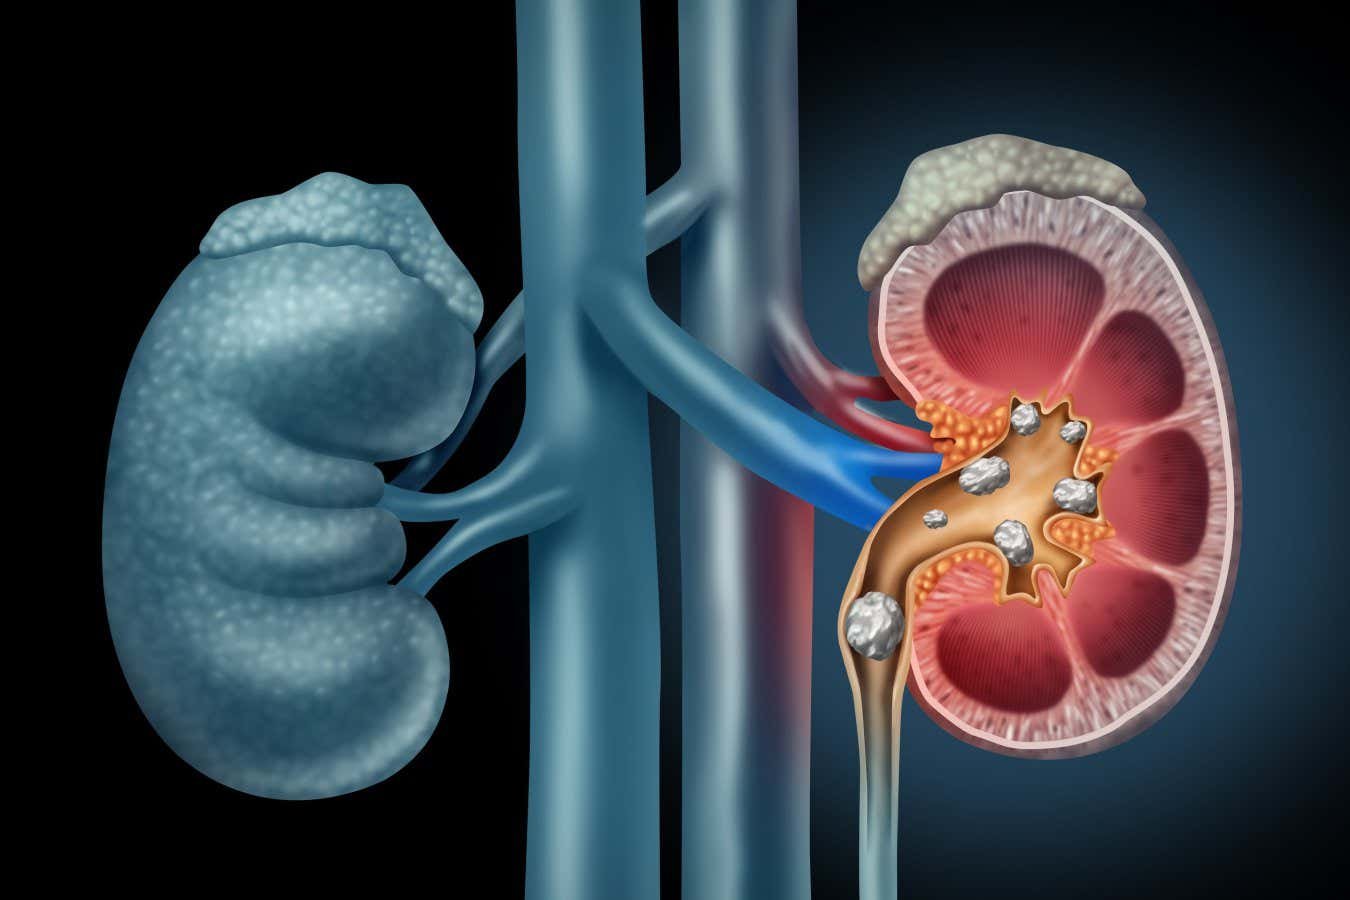

Kidney stones are a common and painful complaint

Kidney stones occur when minerals in urine crystallise. They can be painful when they become lodged inside the kidneys or enter the ureters, tubes that connect the kidneys to the bladder.

Surgeons can then remove the stone fragments, usually one by one, using a wire basket that is fed in and out of the urethra. But this repeated retrieval can cause tissue damage. In about 40 per cent of cases, fragments are left behind, partly because especially small ones slip through the basket. These carry the risk of forming more stones.